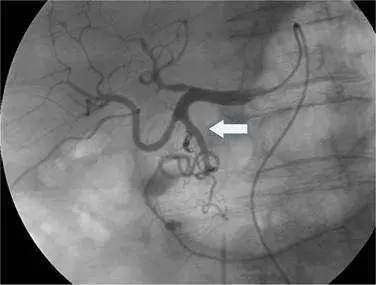

圖片為數位減影血管攝影(digital subtraction angiography, DSA)影像,顯示腹腔動脈幹及其分支系統。白色箭號指向影像中央偏下方的一條迂曲血管,該血管:

- 位於肝總動脈(common hepatic artery)分出後向下方走行

- 呈現迂曲蜿蜒形態,並可見造影劑異常積聚(出血徵象)

- 血管走行方向為向下、朝向十二指腸及胰頭區域

- 此走行方向不符合左胃動脈(向左上)或肝動脈(向右上)的典型走行

根據解剖位置及走行方向,箭號所指為**胃十二指腸動脈(gastroduodenal artery)**出血,可見造影劑外滲形成的血管外積聚影像。